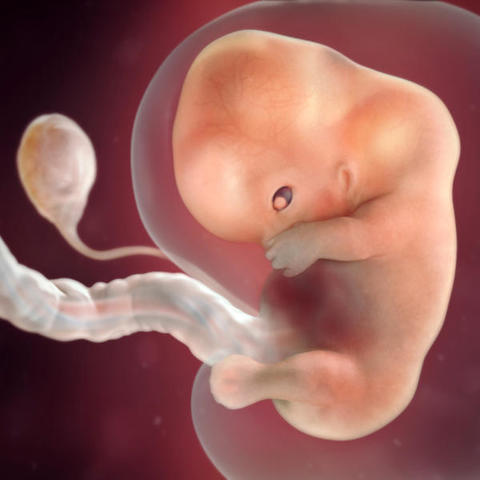

Se desarrolla lo que denominamos embrión, que tiene, básicamente, una cabeza, un tronco y una cola rizada.

Esta semana de embarazo está marcada por:

- La sujeción del blastocisto en el útero, ya que va a ser su “casa” durante todo el embarazo.

- La creación del saco o cavidad amniótica incluido el líquido amniótico..

- La cavidad coriónica, donde estará fijado el embrión sobre un pedículo de fijación, que se transformará en el cordón umbilical.